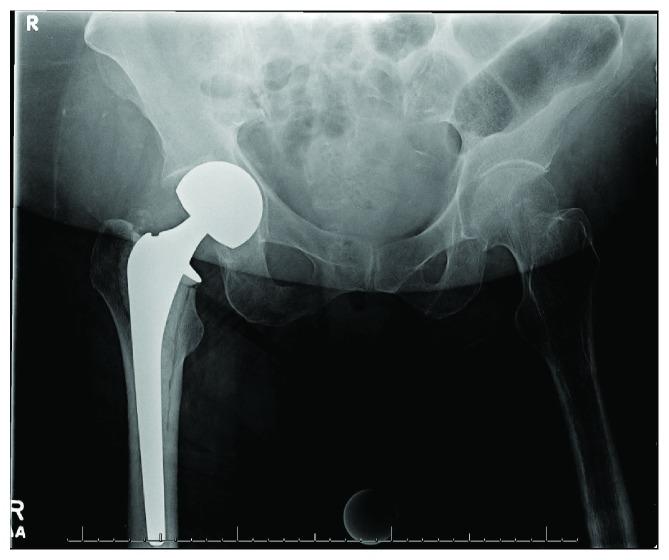

Both hemiarthroplasty and total hip arthroplasty have been well described as effective methods of management for displaced femoral neck fractures in the elderly. Acetabular erosion is a common long-term complication of hemiarthroplasty. We present a case in which rapid acetabular erosion occurs within weeks of hemiarthroplasty, ultimately leading to an acetabular fracture and need for revision to total hip arthroplasty. Early and rapid acetabular erosion following hip hemiarthroplasty has not been well documented in current literature. It may lead to acetabular fracture and may be secondary to infectious causes. If encountered, an infection workup should be initiated.

半髋关节置换术和全髋关节置换术均已被充分描述为治疗老年人移位型股骨颈骨折的有效方法。髋臼侵蚀是半髋关节置换术常见的长期并发症。我们报告一例半髋关节置换术后数周内发生快速髋臼侵蚀的病例,最终导致髋臼骨折并需要翻修为全髋关节置换术。目前文献中尚未充分记录髋关节半置换术后早期快速髋臼侵蚀的情况。它可能导致髋臼骨折,可能继发于感染原因。如果遇到这种情况,应启动感染检查。